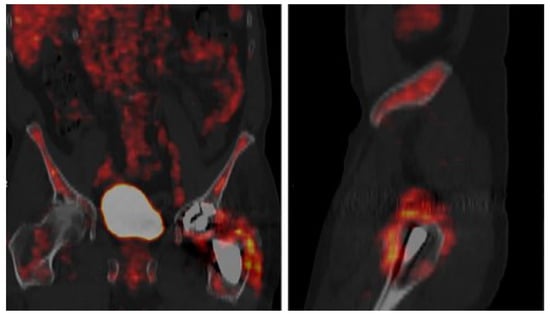

5.5. 18F-Fluorodeoxyglucose Positron Emission Tomography (FDG/PET/CT)

| Multiple (meta-analysis) | 1437/Multi-joint | IO, H, and C | FDG/PET/CT | 85 | 86 | NA | NA | 92 | [109] |

| Denmark | 48/K and H | IO and M | FDG/PET/CT | 100 | 71 | 58 | 100 | 79 | [101] |

| United Kingdom | 130/H | MSIS | FDG/PET | 94.87 | 38.46 | 60.21 | 94.59 | 56.38 | [110] |

| United Kingdom | 55/H | C | FDG/PET | 93.75 | 35.89 | 37.5 | 93.33 | 52.7 | [111] |

| USA | 87/K | H and M | FDG/PET | 94.7 | 88.2 | 69.2 | 98.4 | 89.7 | [100] |

| USA | 134/H | H and M | FDG/PET | 81.8 | 93.1 | 79.4 | 94 | 90.3 | [100] |